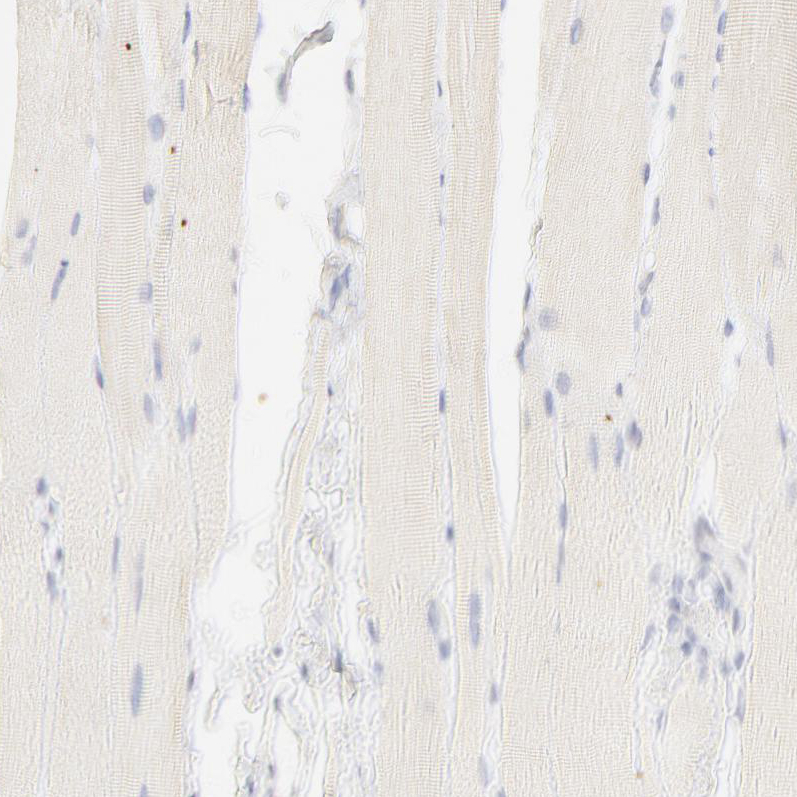

Immunohistochemical staining of human cerebral cortex shows moderate nuclear positivity in glial cells.